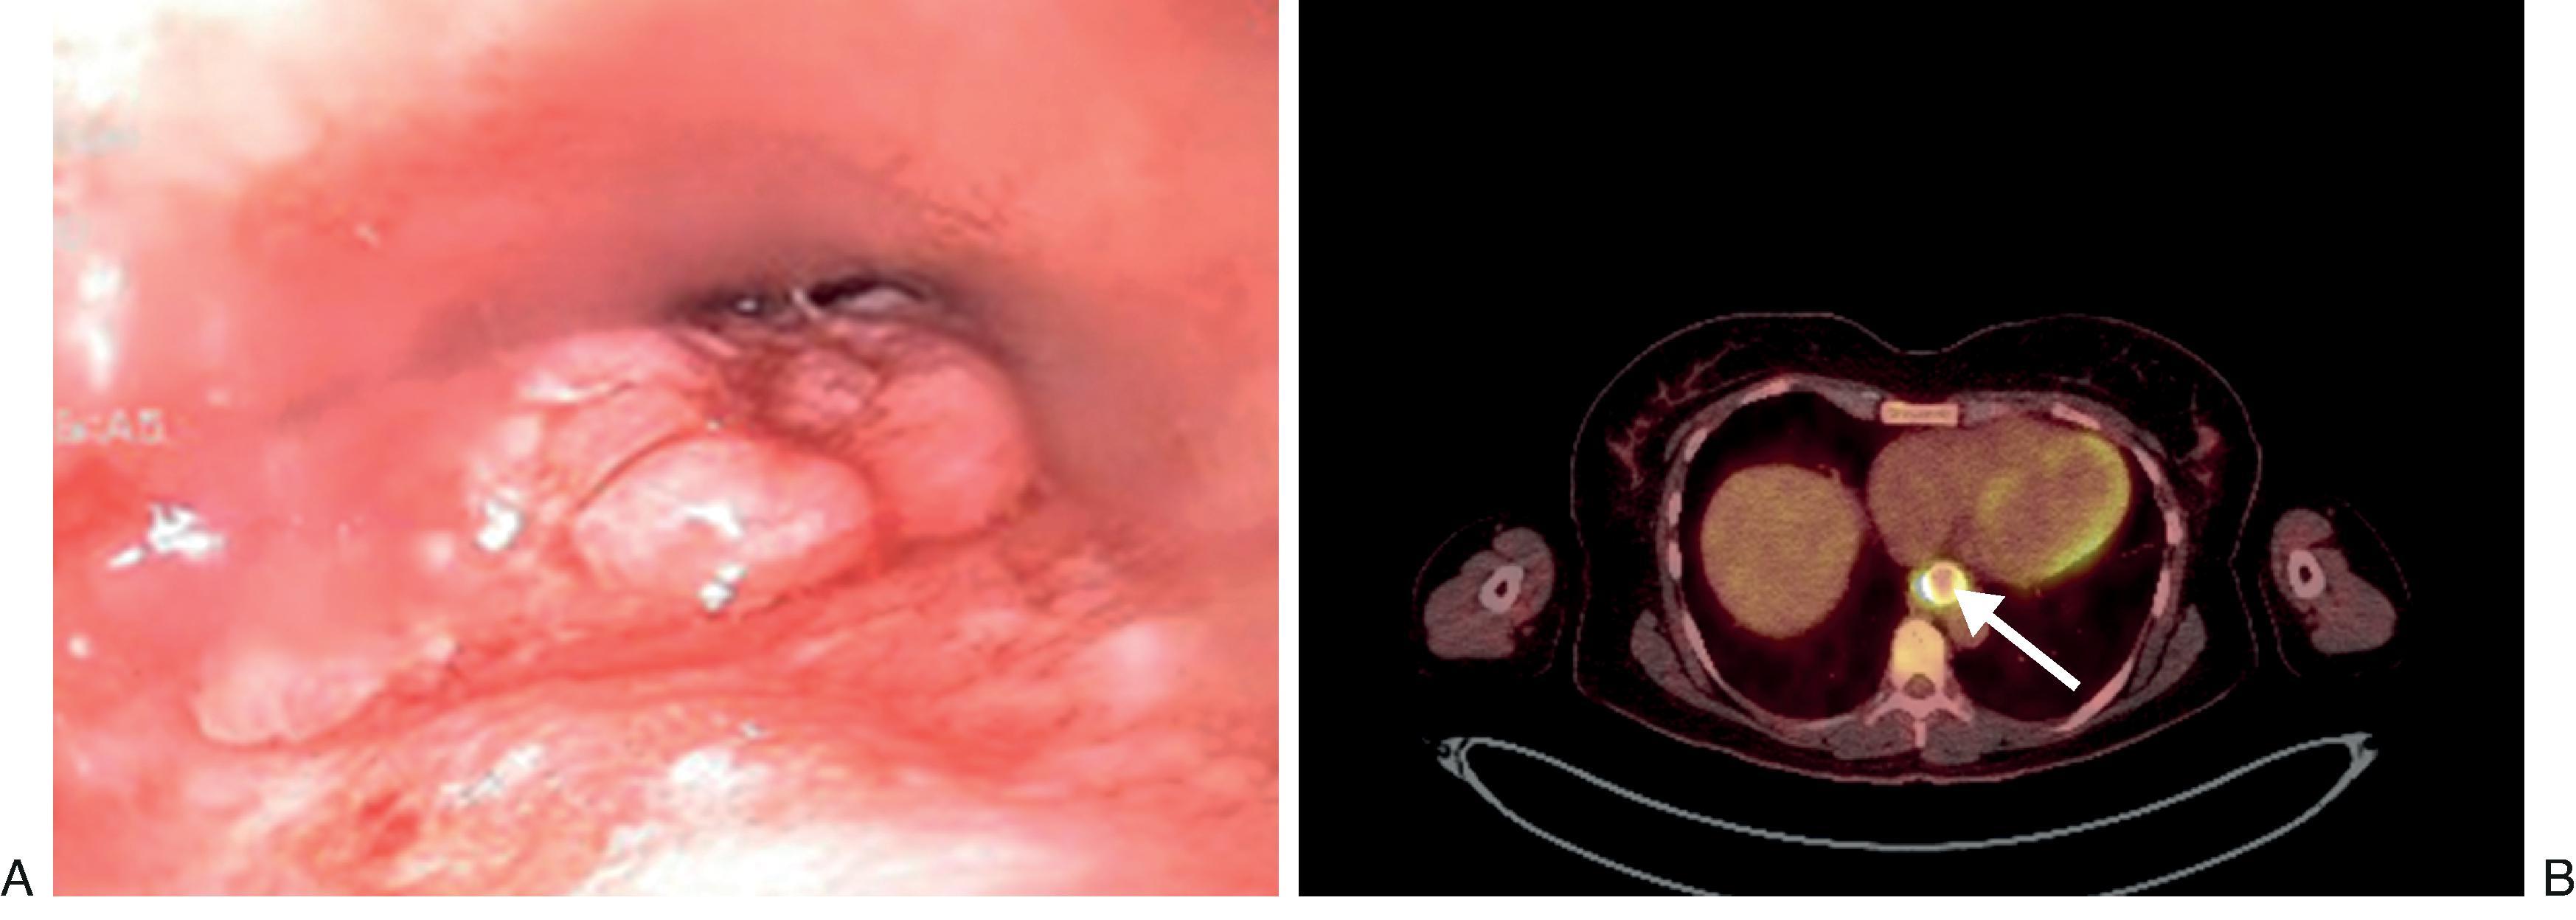

Patients commonly present with dysphagia and weight loss. Diagnosis is obtained with endoscopy. Direct visualization provides information, such as size and location of the mass, and tissue diagnosis is obtained with biopsy forceps. Once the diagnosis is confirmed, clinical stage must be determined ( Table 4.2 ). In esophageal cancer, depth of radial invasion is more important than size in staging. Therefore determining T and N staging is best achieved with endoscopic ultrasound (EUS). Tissue biopsy via ultrasound-guided fine needle aspiration (FNA) can also be performed on suspicious lymph nodes. EUS and EUS-FNA have high sensitivity and specificity in accurately diagnosing T stage and N stage, respectively. However, T2 lesions remain notoriously challenging with an accuracy of approximately 30% because both tumor upstaging and downstaging can occur ( Fig. 4.4 ). Bronchoscopy may be necessary to rule out airway invasion.

• Fig. 4.4, A 35-year-old female diagnosed with a lower esophageal clinical T2N0 adenocarcinoma. She underwent hybrid Ivor-Lewis esophagectomy. Pathology was pT3N2 adenocarcinoma. She subsequently underwent adjuvant chemoradiation ( A and B ). B , PET scan image.